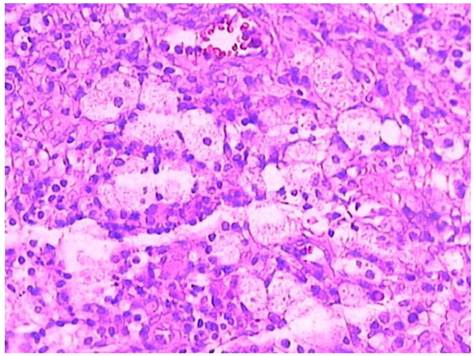

Figure 2

Foamy histiocytes in higher power view (case 1).

Microscopic examination: All specimens were fixed in 10% formalin, dehydrated in descending grades of alcohol, sections were paraffin embedded and processed for histologic and immunohistochemical stains. The pathological changes were composed of mixed inflammatory cells and focal foamy histiocytes. The inflammatory cells were mainly lymphocytes admixed with plasma cells, small number of neutrophils and eosinophils (Figure 1). The foamy histiocytes were focally scattered, with abundant cytoplasm, small lipid vacuoles and hypochromatic nuclei (Figure 2). Multinucleated giant cells were not observed. In the stroma, fibroplasia with fibrosis, vascular proliferation with sclerosis in arterioles, hyperplasia and swelling in blood capillary endothelial lining were observed. The fibrous pseudocapsule was infiltrated with chronic inflammatory cells. Periodic acid-schiff (PAS) and acid fast stains were negative. The subsequent immunohistochemical stains demonstrated positive CD20, CD5, CD79a, κ and λ. The pathological diagnosis rendered as xanthogranulomatous oophoritis.